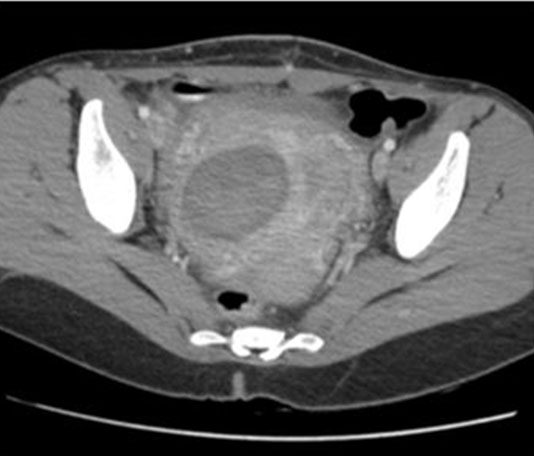

As a result of the patient’s presentation, a transvaginal and transabdominal pelvic ultrasound scan with color and spectral Doppler was ordered. Sonography reports indicated an anteverted uterus (10.6 × 6.5 × 8.5 cm) and a heterogenous solid and cystic myometrial mass (5.7 × 4.5 cm) within the anterior uterus. Right ovary was unremarkable, but the left ovary was unable to be identified, and a small amount of free fluid in the cul de sac (Figure 1). A CT was then ordered, revealing a complex fluid collection (6.7 × 7.2 × 4.7 cm) with an associated area of calcification (Figure 2).

Figure 2: CT abdominal/pelvis confirming complex fluid collection within uterus.